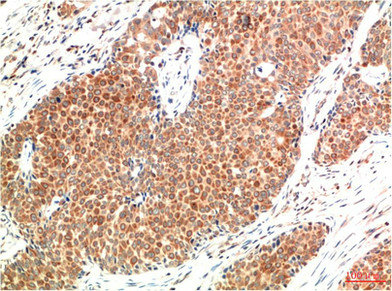

• Immunohistochemical analysis of paraffin-embedded Human Colon Carcinoma Tissue using ATM Mouse mAb diluted at 1:200.

• Immunohistochemical analysis of paraffin-embedded Human Breast Carcinoma Tissue using ATM Mouse mAb diluted at 1:200.